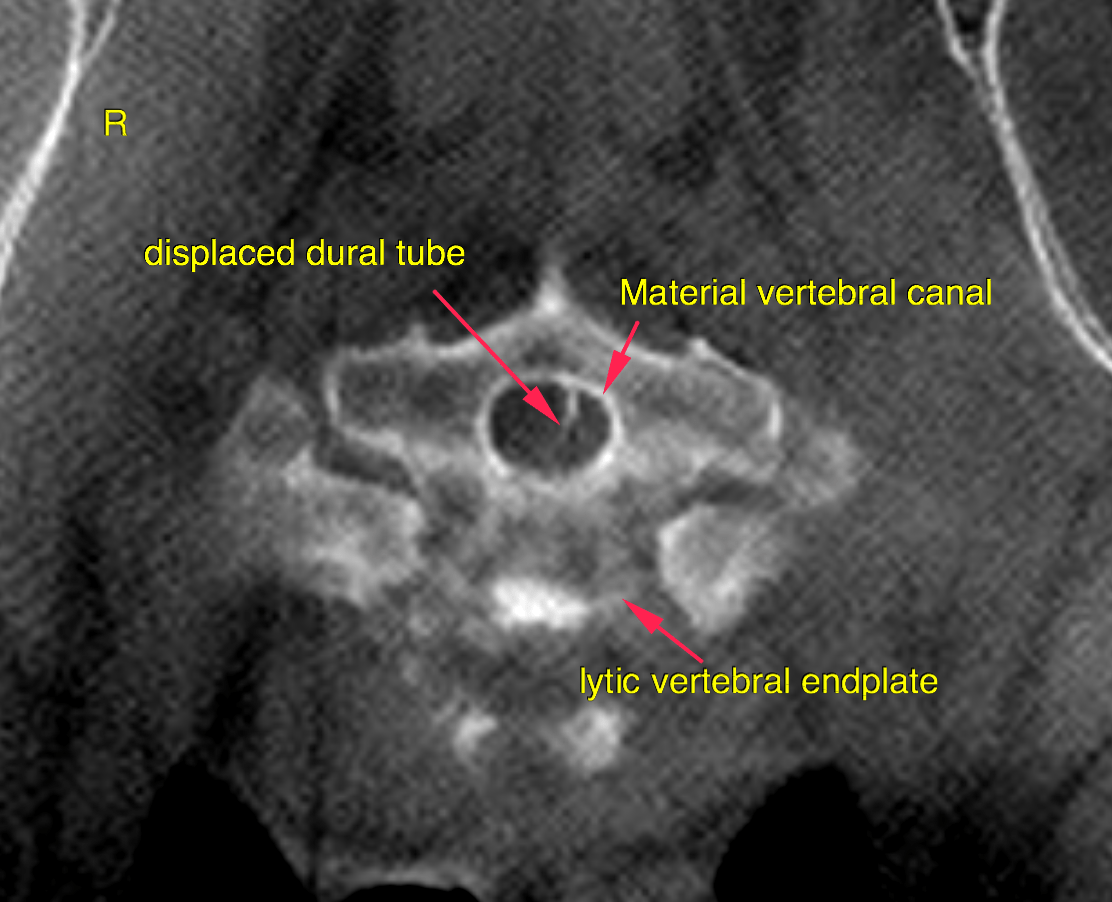

This 6 year old MN German Shepherd dog was diagnosed with hyphema, glaucoma and ocular trauma OD 3 week prior. Presented 2 days ago for ataxia and disorientation; CP deficits noted pelvic limbs. Chem: pre-renal azotemia.